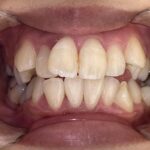

10代女性「前歯が出ていて口が閉じにくい」歯が重なり合って並んでいる「叢生」と上の歯が前に出ている「上顎前突」を、マウスピース型矯正装置「インビザラインフル」で改善した症例

拝見したところ、歯並びの幅が狭くスペースが不足していることにより、全体的に歯が重なり合って並んでいる「叢生(そうせい)」でした。

また、上の歯並びが前方に出ている「上顎前突(じょうがくぜんとつ)」も見られ、唇が閉じにくく口呼吸が増えていました。